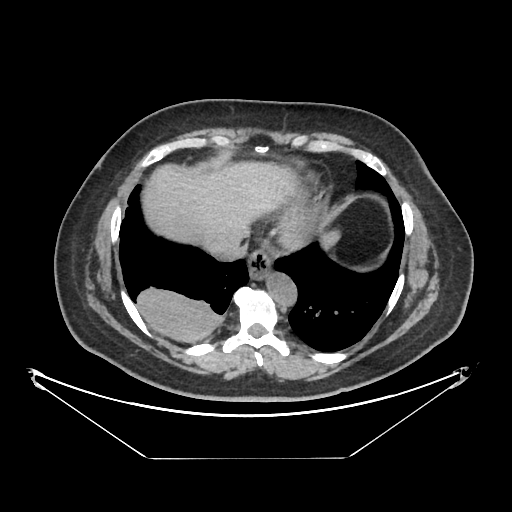

Generated VENOUS CT scan (A→B translation)

Full window (WL 1023.5, WW 4095 β†’ Low βˆ’1024, High +3071)

Actual HU range: [-1024.0, 897.0]

Lung window (WL -600, WW 1500 β†’ Low βˆ’1350, High +150)

Actual HU range: [-1162.5, 150.0]

Mediastinum window (WL 40, WW 400 β†’ Low βˆ’160, High +240)

Actual HU range: [-160.0, 240.0]